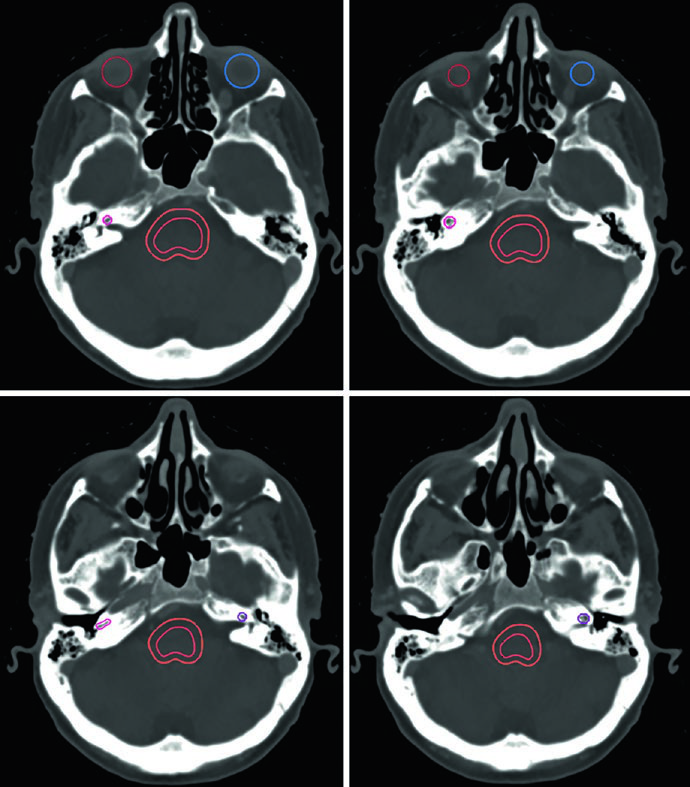

El caso de la Figura 29.9 ilustra un schwannoma vestibular derecho en el ángulo cerebelopontino que comprime el pedúnculo cerebeloso medio y el puente, extendiéndose hasta el fondo del canal auditivo interno. Existe compresión del tronco encefálico y del nervio trigémino cisternal, con borramiento parcial moderado del cuarto ventrículo. En la Figura 29.10, el tratamiento de un schwannoma del APC izquierdo con SRS a 12,5 Gy de prescripción muestra la isodosis de prescripción cubriendo el tumor, con isodosis de 20 Gy en el centro y 5 Gy en la periferia, preservando tronco encefálico y cóclea como OARs.

Los schwannomas vestibulares y no vestibulares pueden tratarse con radioterapia como tratamiento definitivo, adyuvante tras resección parcial o, en casos raros, para recurrencia. Una característica distintiva: no se añade margen de CTV. El GTV se delinea directamente en RM T1 poscontraste y TC de simulación, y únicamente se aplica un margen de PTV dependiente de la técnica.

| SRS | 12–13 Gy en fracción única | Tumor en RM + TC | Ninguno | 0–1 mm |

| FSRT | 20 Gy/4 fracciones o 25 Gy/5 fracciones | Tumor en RM + TC | Ninguno | 0–1 mm |

| RT convencional | 46,8–54 Gy a 1,8–2 Gy/fracción | Tumor en RM + TC | Ninguno | 0–3 mm |